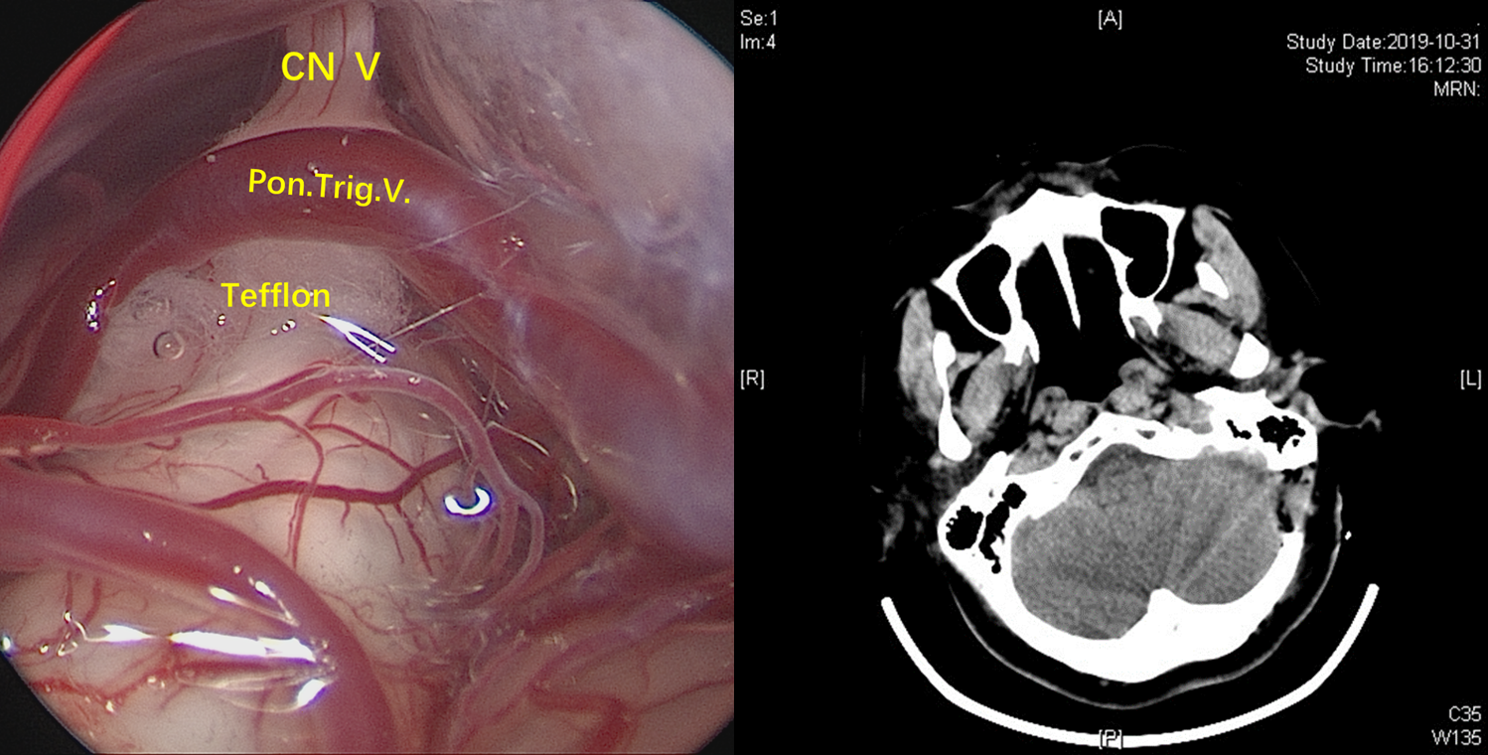

CASE3:右侧三叉神经痛(SCA)

季**,64岁女性

阵发性右颜面部放电样疼痛2年,加重2月

疼痛范围位于右侧三叉神经第三支,口服卡马西平效果不佳,患者手术意愿强烈。

MRTA可见,小脑上动脉与右侧三叉神经关系密切,且与之紧贴,脑池空间(白色)狭小,三叉神经与岩骨距离近。

术中充分释放脑脊液,从面听神经与岩静脉之间的间隙观察三叉神经。

神经内镜抵近观察(岩静脉的阻挡迎刃而解,内镜的优势体现),岩骨、SCA与三叉神经紧贴,减压空间较小。

在不损伤岩静脉的前提下,将责任血管尽可能向小脑与天幕之间移位,使减压尽可能充分。

术后患者疼痛消失,无面部麻木。